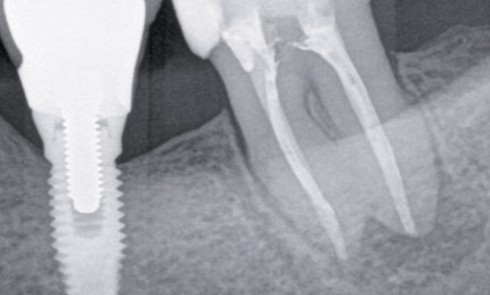

Conserver coûte que coûte grâce à la tolérance de la biologie Une hirondelle ne fait pas le printemps. Néanmoins, quand elle...